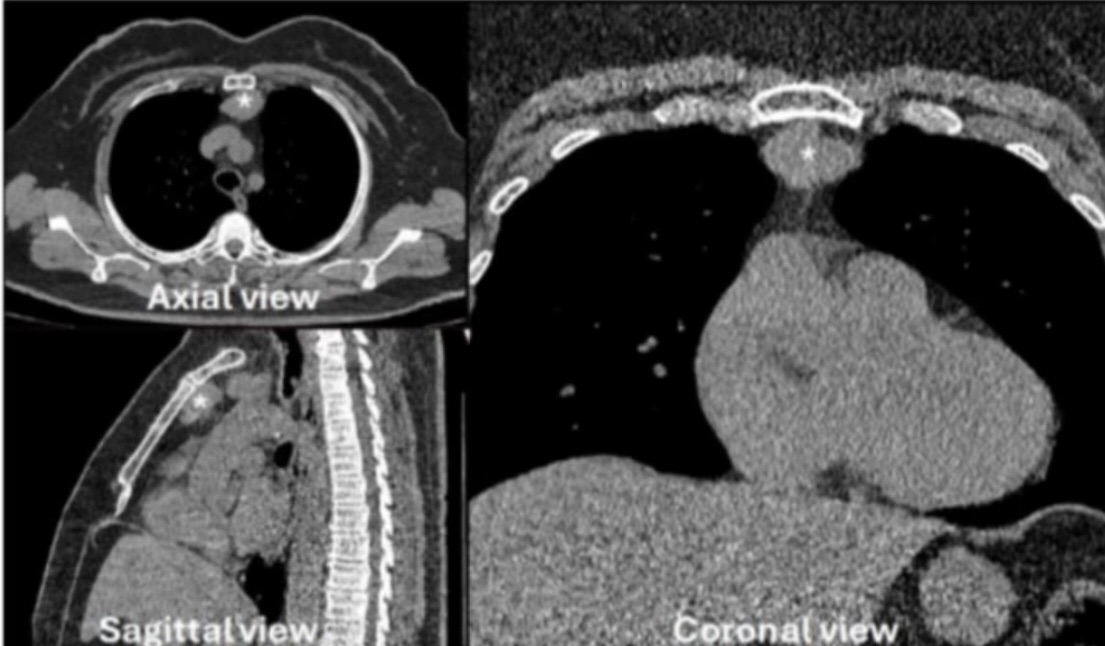

La timectomia robotica con asportazione del grasso mediastinico omolaterale rappresenta l’intervento di scelta per il trattamento del timoma nei pazienti non miastenici. In corso di intervento la pleura mediastinica può essere lesa, l’aria passa nell’emitorace controlaterale con possibile  pneumotorace. La riparazione con punti di sutura della pleura può essere difficoltosa essendo la pleura molto sottile.

Recentemente abbiamo pubblicato sulla rivista internazionale Surgeries (I.F. 1.5) una nuova tecnica di riparazione della pleura mediastinica controlaterale in corso di timectomia robotica mediante posizionamento di patch di cellulosa